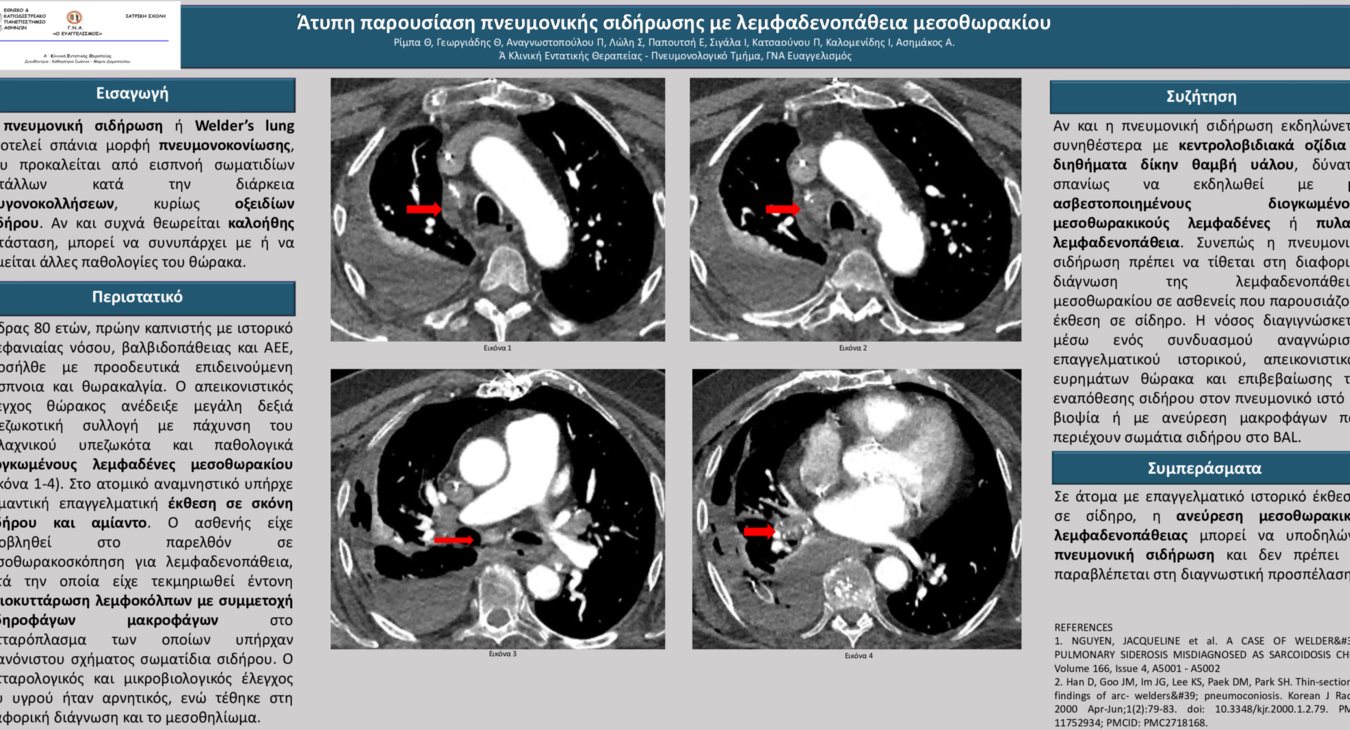

Άτυπη παρουσίαση πνευμονικής σιδήρωσης με λεμφαδενοπάθειαμεσοθωρακίου.